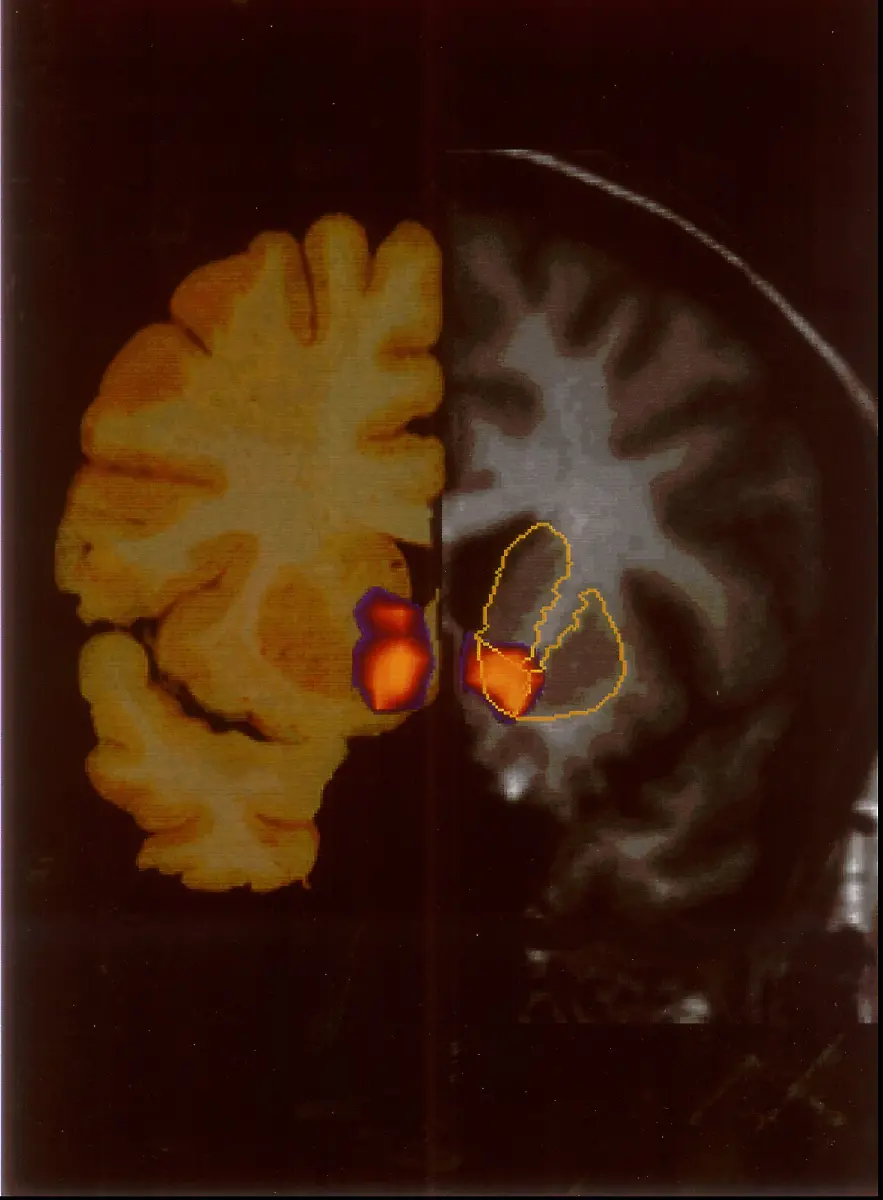

Kokain auf Filmpremieren, Joints bei Studentenpartys und Heroin im Bahnhofsviertel - das ist das Klischee vom Drogenkonsum. Doch Drogensucht gibt es in immer mehr Formen und immer mehr Ländern, wie ein neuer UN-Bericht zeigt.